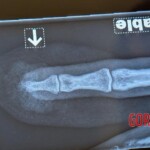

USA – JULY 3, 2025 Dude shared a graphic post online showing the tip of his finger, which had been sliced off by a faulty sliding door. According to his account, the door’s rollers were broken, forcing him to use excessive force to shut it. The accident happened in an instant – he didn’t even realize what was going on until a wave of sharp pain hit him. After getting medical attention at the hospital, he came home only to discover the crushed piece of his fingertip still lodged in the door. The post quickly gained attention, with many people expressing sympathy and sharing similar stories. It also served as a stark reminder of how dangerous neglected home repairs can be, even in everyday situations.